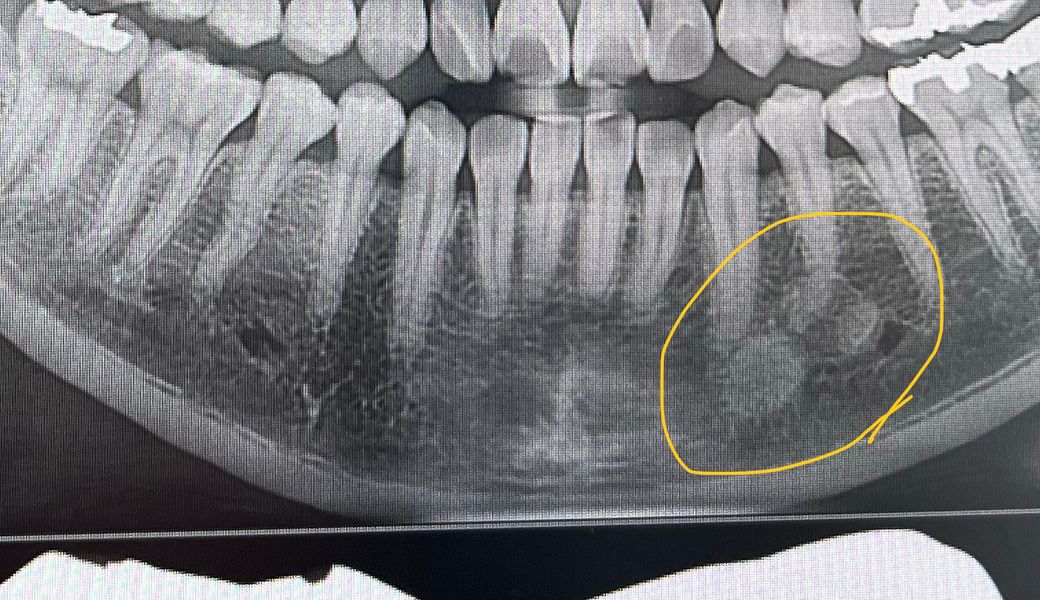

X ray상 턱 아랫부분 동그란 모양이 있는게 뭔가요?

치과에서 엑스레이 사진을 찍었는데 노란색 동그라미 친

모양이 뭔지 궁금해요..뭔가 이상이 있어서 검사를 받아야 하는걸까요? ㅜㅜ

사진만으로는 정확한 판단이 어렵습니다. 타석일 수도 있고, 비대해진 골 등일 수도 있으며 양성종양일 가능성도 있습니다. CT 등의 자료가 필요해보입니다. 따라서 지금 보여주신 사진만으로는 정확한 판단이 어렵습니다. 하지만 앞쪽 mental foramen의 신경과 근접해 보이므로 치과 방문 후 반드시 다시 한 번 상담을 받아보시길 바랍니다.

턱뼈가 석회화가 되셔서 그런겁니다. 크게 문제가 잇는건 아니니 너무 걱정하지 않으셔도 될것같습니다.